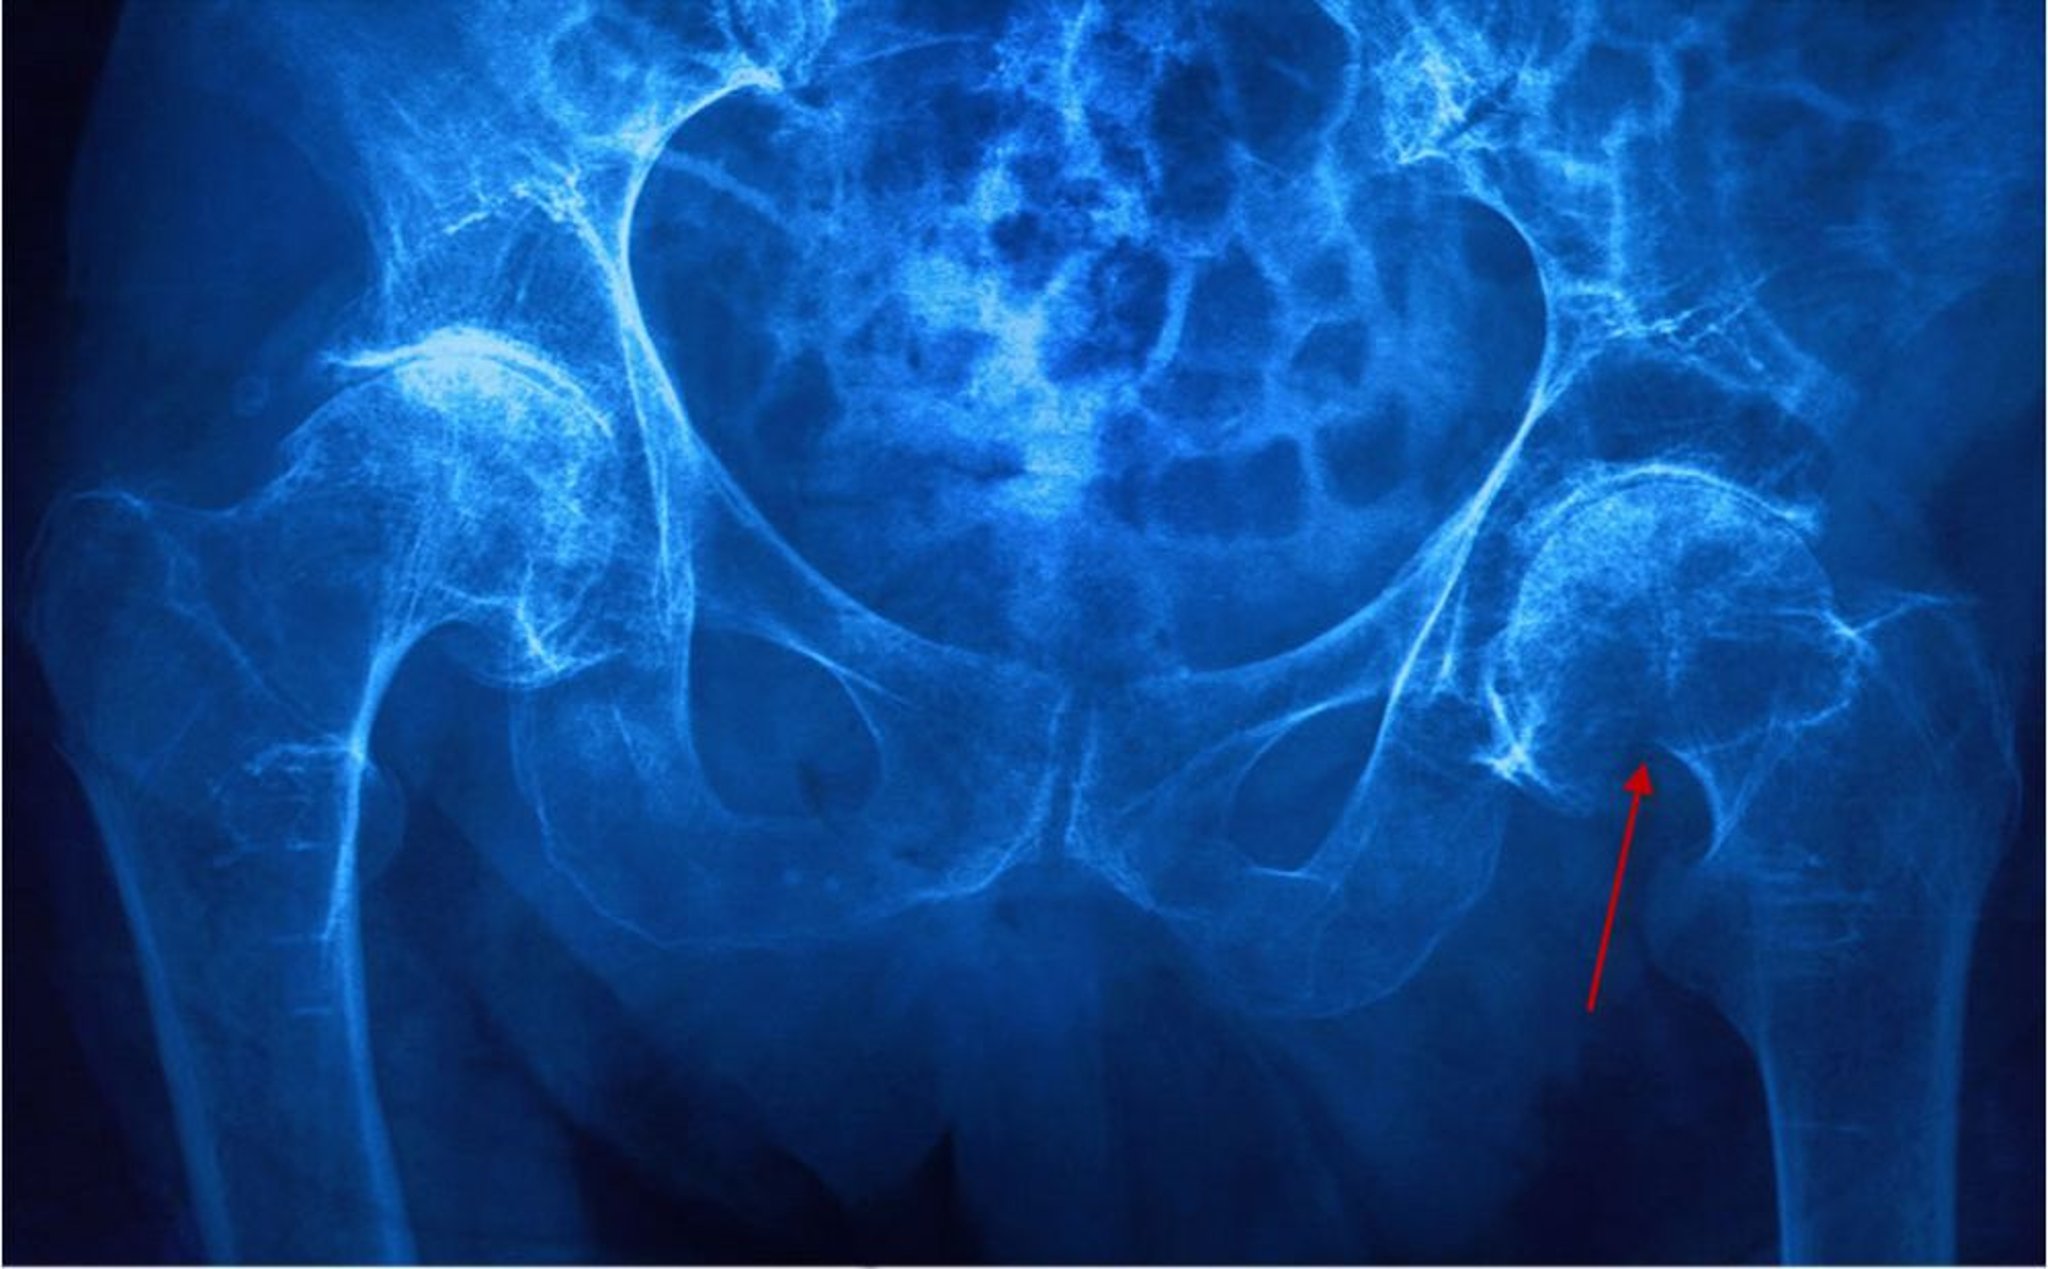

Frattura del collo femorale

Questa radiografia mostra una frattura del collo femorale sinistro (subcapitale) evidenziata da un collo del femore accorciato e da una rottura della corticale (freccia).

CAVALLINI JAMES/BSIP/SCIENCE PHOTO LIBRARY